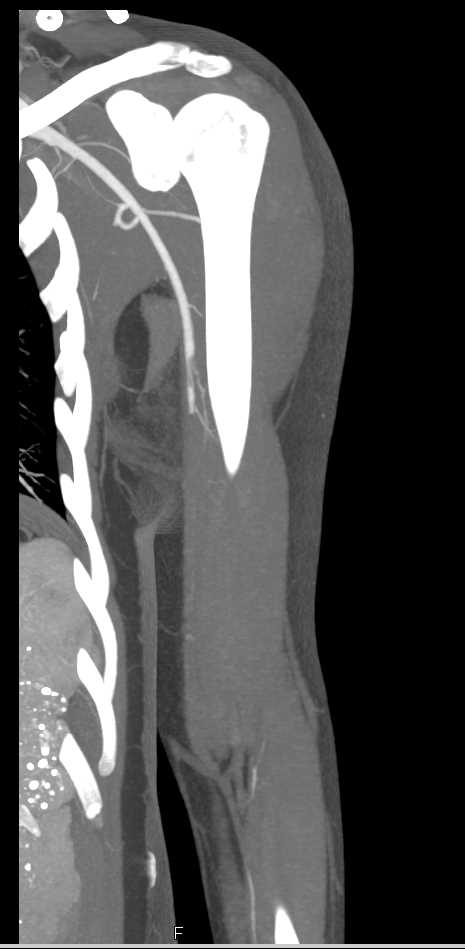

Brachial Artery Occlusion